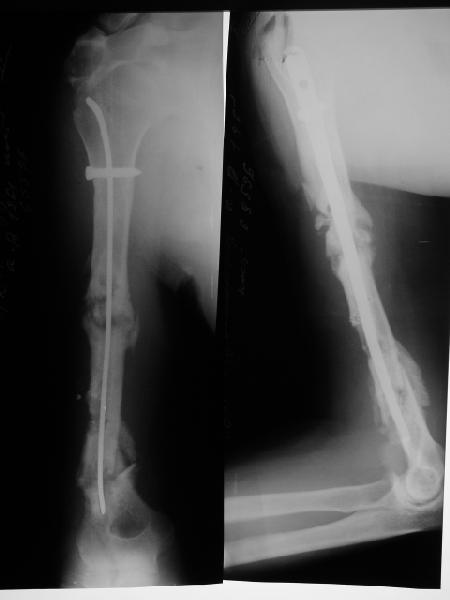

Такие надмыщелковые переломы в изолированном виде у нас в последние годы обычно фиксируются плоским титановым стержнем a la Зверев-Ключевский антеградно. Но тут еще и вышележащие проблемы.

Наверно, можно пойти на укорочение, убрав металлический цилиндр, не такой уж большой дефект. Снимки в чем-то похожего пациента прилагаю - тоже несращение диафиза после многократных операций, и надмыщелковый свежий перелом (случился после удаления обломка стержня аппарата).